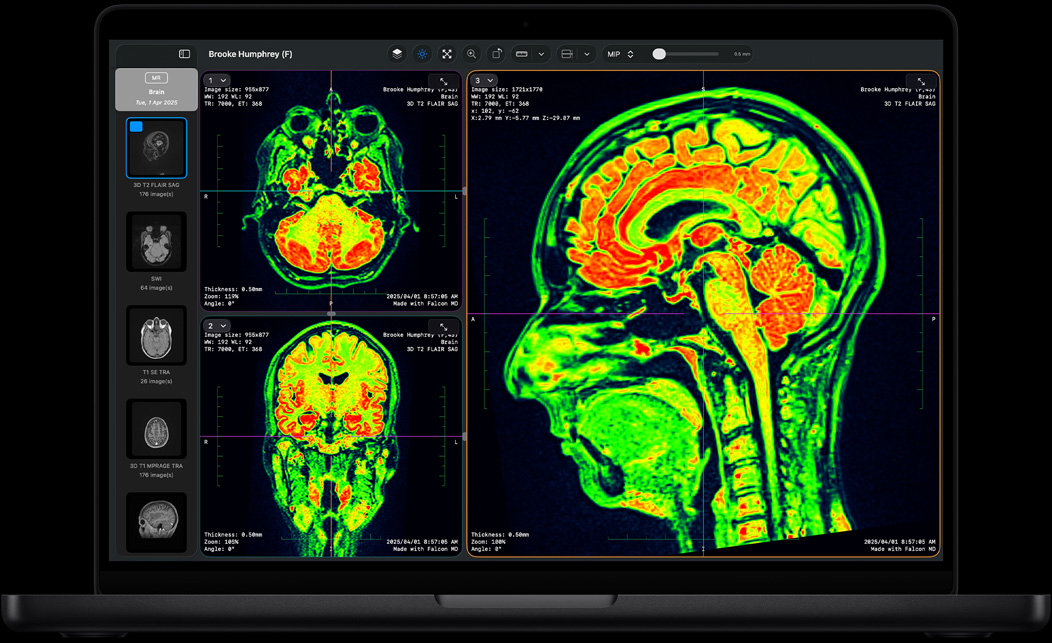

Falcon MD

لكل من يسعى إلى الارتقاء بقوة الأداء، شريحة M4 Pro تسرّع كل المهام على اختلافها، من تصميم قواعد البيانات ونمذجة البيانات إلى تحديد تسلسل الحمض النووي. وسواء اخترت موديل 14 إنش أو 16 إنش، يتفوّق MacBook Pro بشريحة M4 Pro في إتمام أصعب المهام بكل سهولة، ويقدم أداء رسومات غرافيك يتيح لك تصيير الرسومات ثلاثية الأبعاد وتحريكها بسرعات أكبر.

MATLAB، وAutodesk AutoCAD، وNASA TetrUSS، وOxford Nanopore MinKNOW، وOsiriX MD، وShapr3D، وSurgicalAR، وVectorworks، وArchicad، والمزيد.